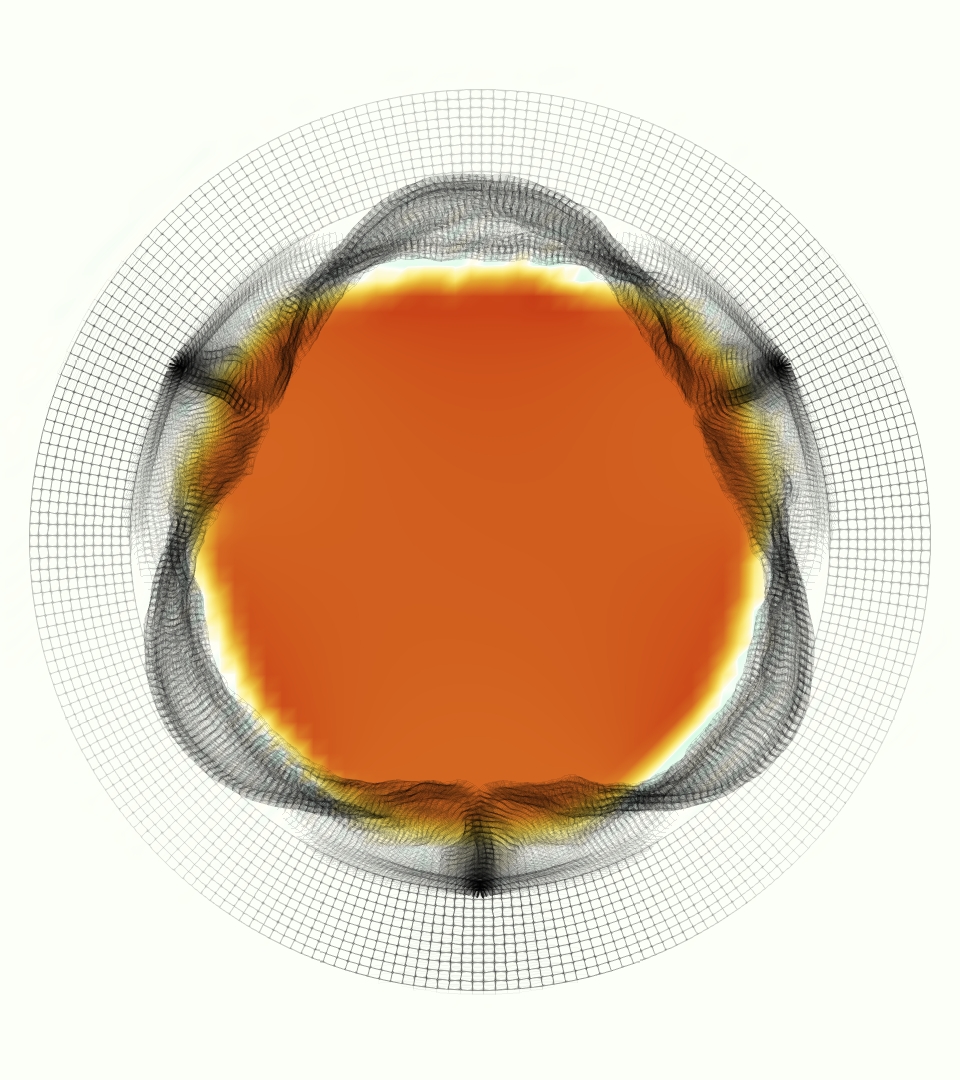

The gross morphology of the model valve that emerged from this process is shown in Figure 4. The free edge was 2.87 cm, corresponding to 3.3 cm in the predicted loaded configuration. After the pinching the leaflets together at the commissures, this left approximately 2.1 cm of free edge rest length per leaflet free to move independently of the other leaflets, within measurement error of ±0.1 cm from the free edge length of 2.2 cm measured on the prostheses. The leaflet rest height was 0.94 cm corresponding to a predicted loaded height of 1.44 cm. The measured leaflet height of 1.3 cm is nearly the predicted loaded height of 1.44 cm, which may be because the leaflets are so compliant in the radial direction, that pulling them flat to measure them achieved substantial stretches. The fiber orientation of the model runs from commissure to commissure and qualitatively matches experimental observations [38], though direct quantitative comparison is beyond the scope of this work. One minor limitation is that we do not add bending rigidity to the leaflets, beyond what emerges from the thickening process described above, and thus may not accurately capture leaflet flutter or other similar behaviors. Based on the thickness of mm, we estimated the mean tangent modulus at the predicted loaded stretches as dynes/cm2 circumferentially and dynes/cm2 radially. The prosthetic valve tissue is fixed in glutaraldehyde, and literature values for the fully-recruited circumferential tangent modulus of fixed porcine aortic valve tissue vary widely. Based on the experimental measurements of Billiar and Sacks and their constitutive law for valves fixed under 4 mmHg of pressure, we evaluated their constitutive law at the relevant stretches and and estimated the circumferential tangent modulus to be dynes/cm2 [6]. Rousseau et al. reported moduli ranging from to dynes/cm2, depending on the applied preload during fixation [36]. Sung et al. reported moduli ranging from to dynes/cm2, depending on fixation pressure [43]. Thus our estimated tangent modulus falls within the range of existing studies, so we considered our resultant modulus in good agreement given the complexity of the steps involved, phenomenological nature of the constitutive law and uncertainties in experiments. We do not have access to the precise material properties of the prosthetic valve, and further, the only literature we could find on the material properties of a similar prostheses reported the tangent modulus at one particular loading, which did not appear to be at a relevant stretch for comparisons with our model [19]. Thus, our model has material properties in a reasonable range for a fixed aortic valve prostheses (placed in the pulmonary position in our simulations), but it does not directly model the material properties of the prostheses.

We constructed the model vessel for FSI simulations from data from the MRI scans (Figure 4). The signal magnitude of 3D printed model material is distinct from the signal of the fluid in the scans, and we applied a thresholding operation to generate a three-dimensional model of the printed vessel surface. Using the MRI data ensured that the MRI and simulation coordinates were consistent in space and there were no alignment or registration errors. While using the files that generated the 3D printed model would have offered more spatial fidelity, the potential error in flow fields due to any mis-registration would have likely been much more substantial. Using Meshmixer (San Rafael, CA), we smoothed the mesh to remove stair-step effects and removed artifacts from the valve scaffold. We then remeshed to the desired edge length of 0.25 mm and extruded the model 0.25 mm and 0.5 mm to create a three-layer structure. As in the valve, this serves to eliminate the “grid aligned artifact” that can occur with pressure differences across thin membranes in the IB method [16]. Flow extenders of length 1 cm were added to the vessel at the inlet and both outlets to ensure that the normal to the vessel was aligned with the normal of the fluid box at the inlets and outlets. In FSI simulations, the vessel was held in place using target points, stiff springs of zero rest length that connect the current position of each model node to its desired position (Section 3.3). Additional linear springs are placed on each edge in the triangulated model. These springs are not meant to model a particular material and only serve to keep the vessel rigid and stationary throughout the simulation.

At = 0, the axial slice directly at the valve annulus shown in columns 1 and 2 in Figure 6, there was excellent agreement between the simulation and experiment over the cardiac cycle in the speed and shape of the jet through the valve. In both cases, the axial velocity increased as the flow accelerated during systole and the valve leaflets opened, then decreased during diastole with slight negative velocity before the valve leaflets were fully closed. The forward flow through the valve annulus did not form a full circle, but rather developed a triangular shape with a point of the triangle forming along the interior curve of the vessel, at the bottom of the axial slices. At = 0, the points of this triangular jet shape aligned with the commissures of the valve. This shape persisted during peak systole and was well-matched by the simulation.

The axial slice = 0.625 cm, shown in columns 3 and 4 in Figure 6, cut through the support scaffolding of the valve and the leaflets when they are open. In the experimental data, the shape of the jet changed as it moved downstream. A triangular shape occurred, but the points were then aligned with the middle of each open leaflet as opposed to the commissures. Those points were also more rounded than they were at = 0. The peak velocity of the jet was faster at = 0.625 cm than at = 0, as the flow accelerated through the open valve leaflets. The simulation produced these features at = 0.625 cm. The triangular shape of the jet shifted similarly, and its speed increased compared to the upstream slice. As the flow decelerated into diastole, the jet shape remained roughly triangular but diminished in intensity before disappearing after valve closure.

The jet continued to develop at = 1.25 cm, an axial slice immediately downstream of the valve scaffolding and open leaflets, shown in columns 5 and 6 in Figure 6. In the experimental data, the points of the triangular jet shape extended further towards the vessel wall. In addition, regions of reversed flow developed in the locations downstream of the commissures, resulting in curved sides to the shape of the jet. Each tip of the jet was unique, due to variations in the individual leaflets in the physical bioprosthetic valve. These variations are apparent in the velocity fields, possibly because the jet edges are similar enough cycle to cycle that irregularities are still being captured even with phase averaging. Further discussion of these features can be found in Schiavone et al. [39], which showed that the jet tip shapes occurred in different pulmonary anatomies, demonstrating that they were likely due to inherent properties of each leaflet. The leaflets in the mathematical model of the valve are identical, so these nuances in leaflet variation could not be replicated. The simulation did capture some of the extension of the tips of the jet, as they were closer to vessel wall at slice = 1.25 cm than = 0.625 cm. The curves in the triangular sides of the jet were also present in the simulation, though they were less pronounced than the experimental data. At both = 0.625 cm and = 1.25 cm, the jet shape in the simulation was smoother than the jet in experiment. It is possible that the free edges of the leaflets in the mathematical model are not fully replicating the behavior of the physical leaflets of the bioprosthetic valve, in particular the amplitude or frequency of leaflet flutter, leading to the variations seen in the jet shape at = 1.25 cm downstream of the leaflet edges. The simulation, however, does capture the key features of the triangular shape and speed of the jet. Overall, qualitative comparisons demonstrated that the simulation reproduced key features of the flow during systole and diastole.

The phase-averaged, resampled velocity fields during peak systole and flow rates at each resolution are shown in Figure 10. Despite the limitations discussed above, we observe similar qualitative trends in the flow field at all resolutions. At all resolutions, a jet formed and angled up downstream of the valve orifice, as shown in the sagittal view. The jets showed a triangle-like cross section at with points aligned with the commissures. At cm, the jet appears like a rounded triangle in the opposing orientation, with its points aligned with the center of the leaflets. At cm, the jet is narrower downstream of the commissures, and wider downstream of the leaflets, again with a triangle-like cross section. The area of the jet increased with resolution, as expected given the IB method thickening of the valve structure. The narrowed jets at the two more coarse resolutions show locally elevated velocities relative to the two more fine resolutions. Figure 11 shows the instantaneous velocity fields at each resolution in the same axial and sagittal views. At 0.9 mm, the sagittal view shows a qualitatively different jet than at finer resolutions, with regions of lower velocity farther from the vessel wall, indicating insufficient resolution. At 0.9 and 0.68 mm, the jet is visibly narrowed compared to higher resolutions. While some features are similar at these two coarse resolutions, we conclude that the narrower jets indicate these simulations are under-resolved. Flows in the three finest resolutions, 0.45, 0.34 and 0.28 mm. appeared qualitatively similar, with slightly more fine structure detail in both the axial and sagittal views present at the edges of the jet. The jets in the axial views all showed a similar triangle-like cross section, slightly narrower downstream of the commissures, as in the phase-averaged fields. In both the phase-averaged and instantaneous fields, the three finest resolutions appear sufficiently similar that the conclusions of this study would be identical with any of these resolutions.